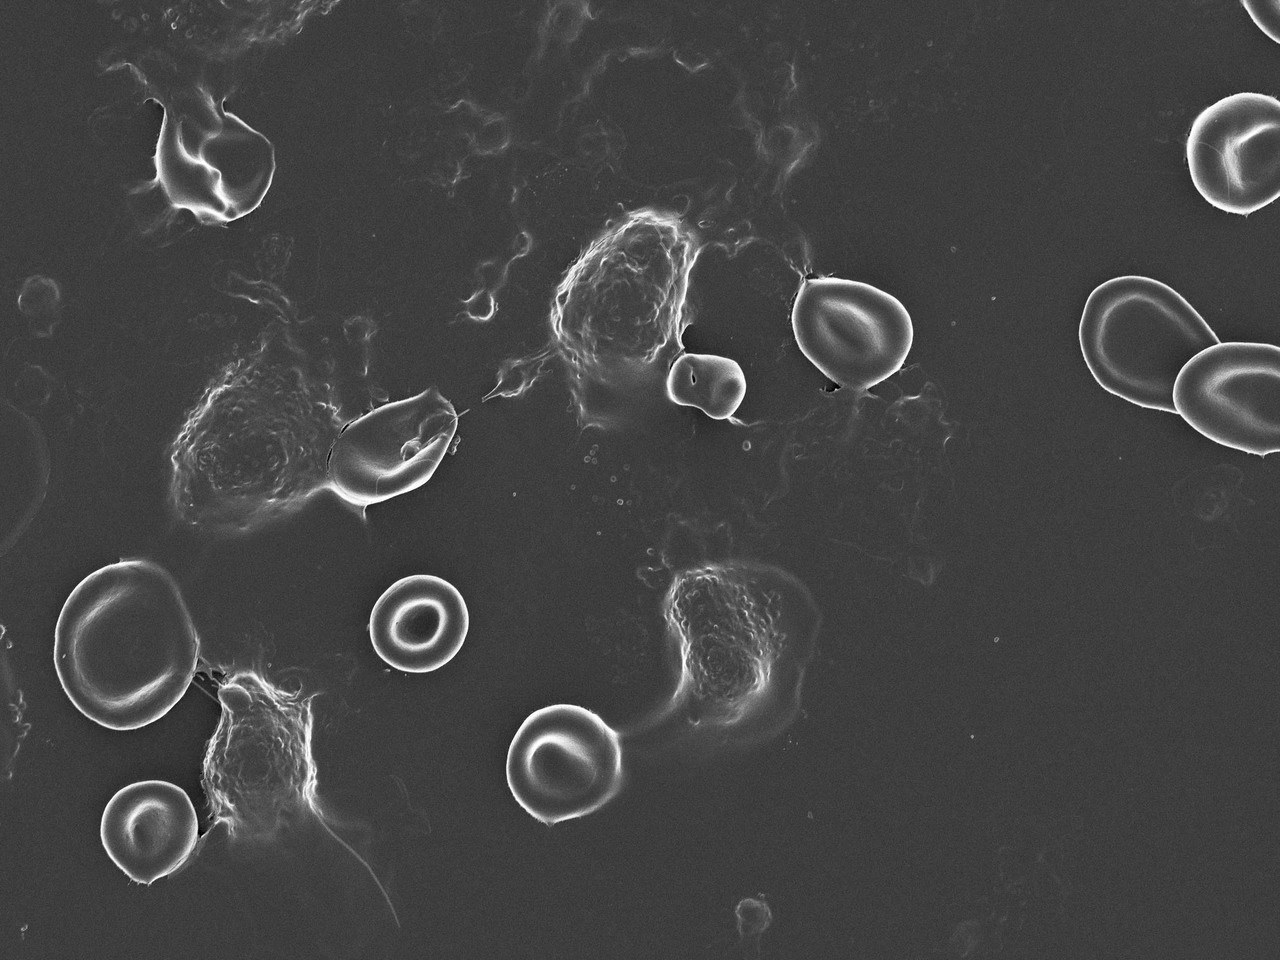

One of us, Willem de Villiers, is a gastroenterologist and an expert in Inflammatory Bowel Disease. He has often noticed in the clinical setting that patients who experience flares of their chronic intestinal inflammation or who suffer from CRC also are more likely to have complications such as venous thrombosis (hypercoagulability). This paper investigated the presence of circulating lipopolysaccharide (LPS) and other circulating biomarkers, indicative of systemic inflammation and abnormal clot formation, in healthy individuals and patients with newly diagnosed CRC.

We showed that circulating levels of LPS are significantly elevated in the CRC population. Moreover, markers of inflammation and hypercoagulability are also increased in this population. Statistical regression models identified markers with strong association with CRC, and we investigated the correlation between these markers. A core aim of our study was therefore biomarker discovery for CRC across a wide range of groups (see Figure 1).